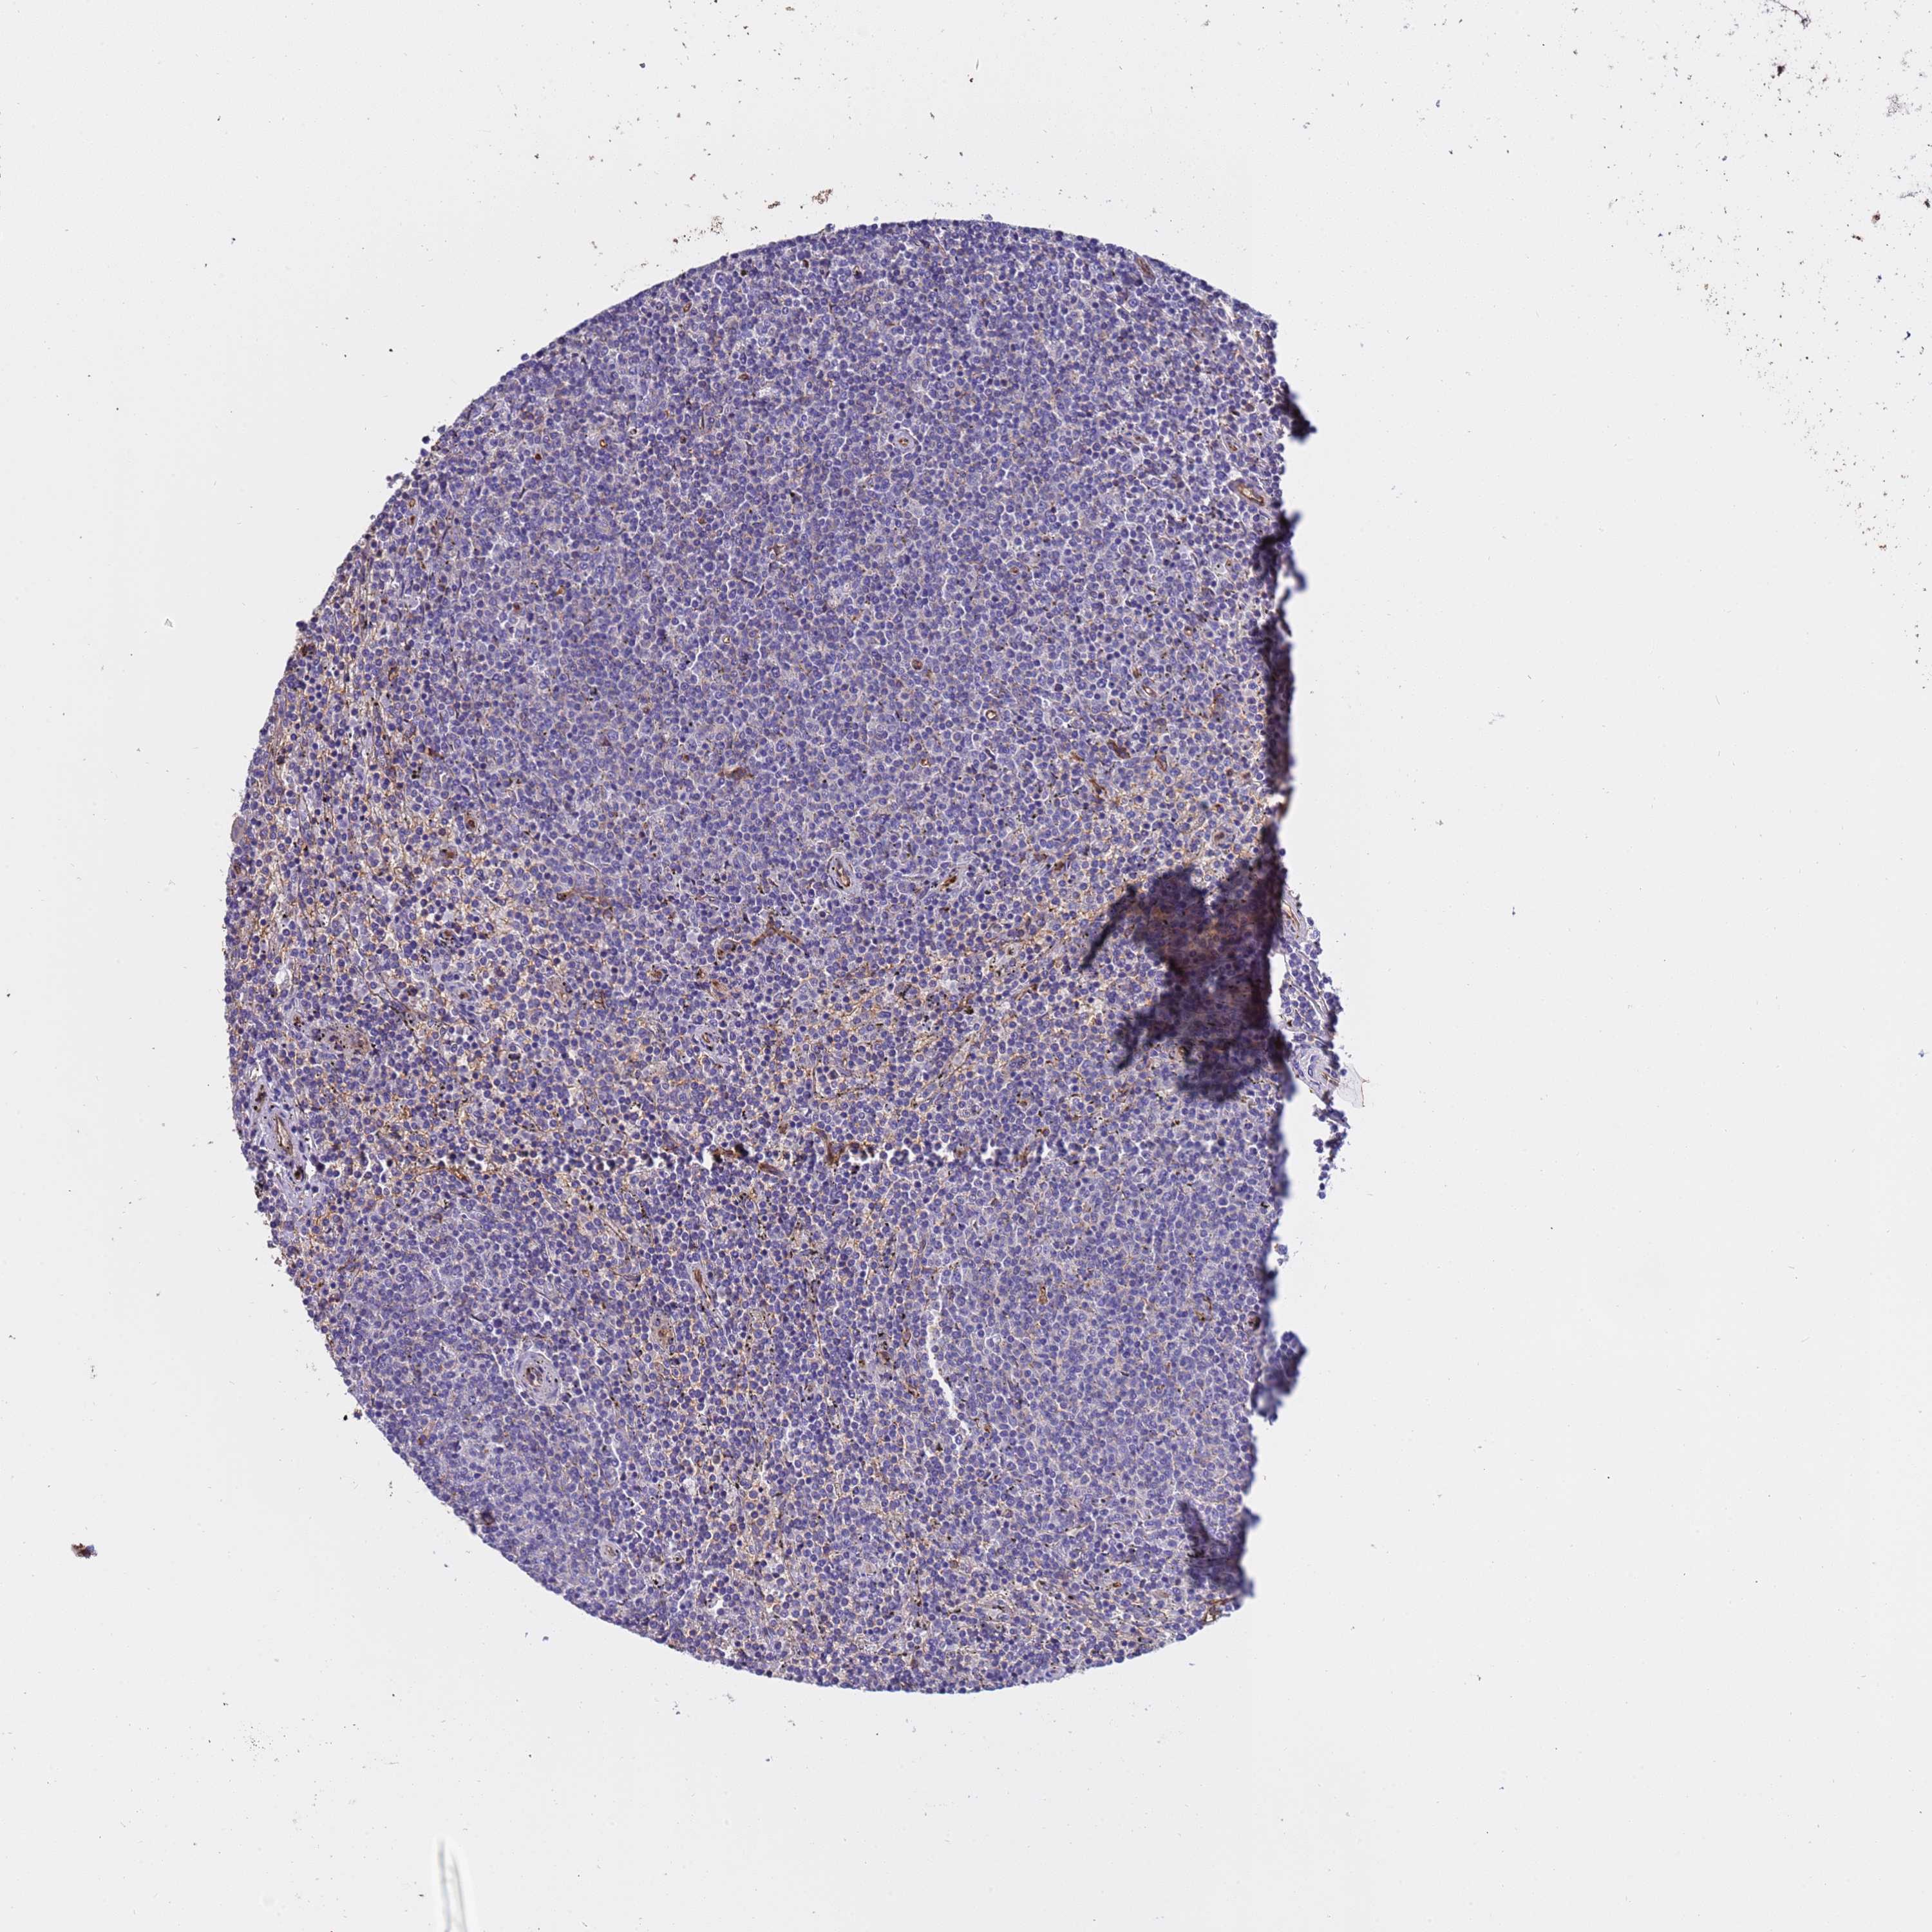

CANCER LYMPHOMA Show tissue menu

LYMPHOMA - Protein expressioni

A mouse-over function shows sample information and annotation data. Click on an image to view it in a full screen mode. Samples can be filtered based on level of antibody staining by selecting one or several of the following categories: high, medium, low and not detected. The assay and annotation is described here.

Each image is clickable and will lead to virtual microscopy that enables deeper exploration of all samples and also displays staining intensity scores, fraction scores and subcellular localization as well as patient and tissue information for each sample.

Antibody HPA018455

Hodgkin's disease, NOS

Malignant lymphoma, non-Hodgkin's type, High grade

Malignant lymphoma, non-Hodgkin's type, Low grade